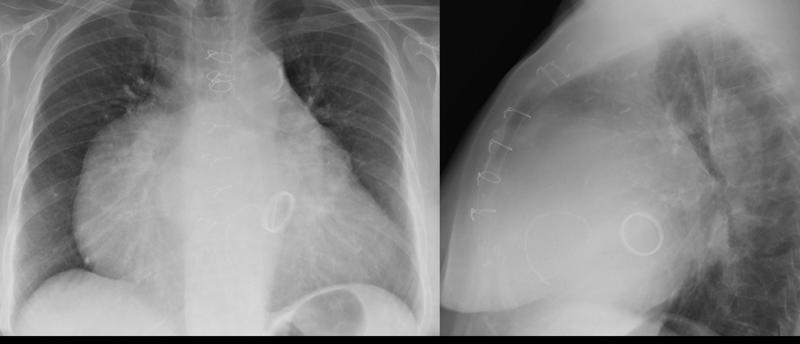

Giant RA PALat